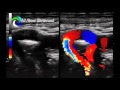

Fetal Echo Mastery Course

Wrapping up an incredible journey in fetal echo 🫀💜💙

Our Fetal Echo Cross Training Course is coming to a close, and what a way to finish — strong, confident, and truly transformed in how we approach fetal cardiac imaging from a cardiology standpoint.

Over these past weeks, our learners have gone far beyond just “learning views”… they’ve built a framework for understanding fetal cardiac physiology and pathology.

• Color and spectral Doppler assessment across all key structures

• Fetal hemodynamics and flow patterns

• Congenital heart disease — from recognition & assessment on echo to interpretation

• Cardiac function (including MPI/Tei Index and ventricular performance)